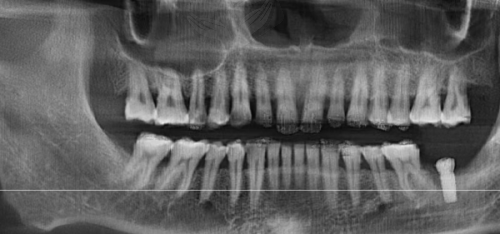

在设备方面,医院配备了精良的口腔医疗设备,有CBCT机、全景机、超声洁治器、铸造机、切割装置、根管测量仪、根管填充器、激光设备、电动吸引器和口腔内窥镜等,为精细诊疗提供了有力保护。www.haohanprint.com

该门诊主要经营项目包括口腔种植、口腔矫正、口腔美容、口腔修复、儿童口腔和口腔综合治疗。特别擅长牙周治疗、烤瓷牙、儿童牙科、活动义齿、牙套、拔牙和牙齿矫正等项目。而且,友好门诊采用国内外精良的口腔诊疗技术,如数字化种植技术和隐形矫正技术,能为患者提供更加精细和舒适的诊疗服务。同时,门诊注重口腔预防保健,还会定期开展健康讲座和义诊活动。